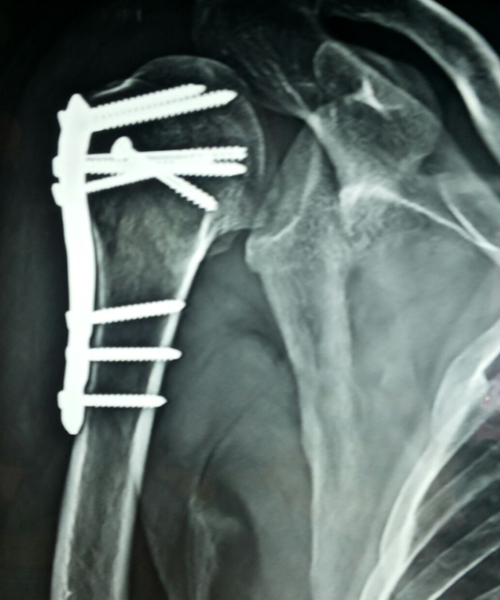

Case:18 Comminuted Fracture Upper Humerus

Female 65 years sustained fall in the house had displaced fracture of head of left Humerus with displaced fragment of greater tuberosity was treated with open deduction and philos plate fixation.

Pre-Op-Xray

Pre-Op CT Scan

CT Scan lateral

Post-Op Xray